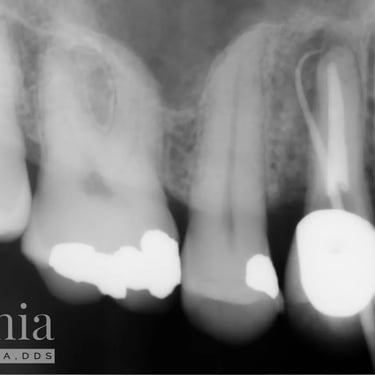

Hipercementosis

La hipercementosis es un engrosamiento anormal del cemento radicular del diente, a menudo debido a una inflamación crónica o trauma.

Los pacientes generalmente no tienen síntomas, pero la condición puede ser descubierta en una radiografía.

El tratamiento no suele ser necesario a menos que cause problemas con la extracción del diente.

Calcificación Pulpar

La calcificación pulpar es la formación de depósitos de calcio dentro de la pulpa dental, que puede dificultar el tratamiento de conducto.

Los pacientes generalmente no tienen síntomas, pero pueden experimentar sensibilidad.

El tratamiento incluye la eliminación de los depósitos durante el tratamiento de conducto. Es importante tratarlo para evitar complicaciones durante el procedimiento.